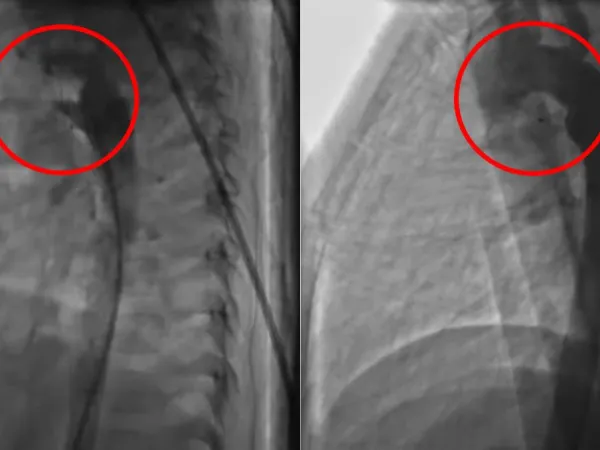

小兒開放性動脈導管 心導管手術助二歲童恢復健康

兩歲的胡小弟(化名),被醫師診斷出有「開放性動脈導管」,經花蓮慈濟醫院兒童急重症科主任暨小兒心臟科醫師裘品筠以心導管治療後,胡媽媽發現恢復健康的胡小弟變得更活潑,她也放下心中的擔憂。   胡小弟平常...